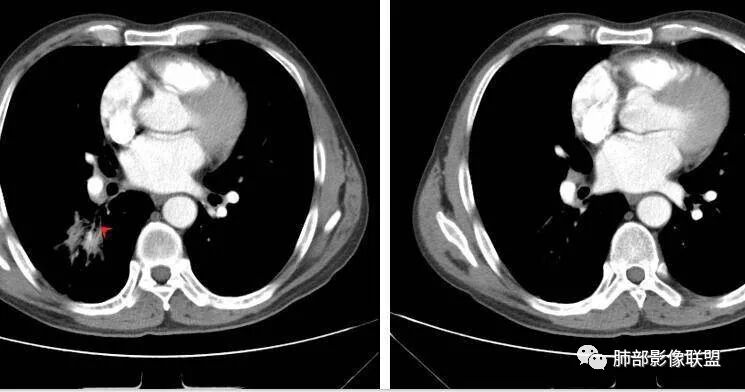

M-Imaging :病人胸痛20天,病灶三角形宽基底与胸膜贴近,肺门侧支气管通畅,造影显示肺动脉狭窄,考虑肺动脉栓塞,肺梗死?HeKate·Awizard·Sinitici:老师,请教一下,这是联盟讲座里说到的支气管爬行征吗?M-Imaging :我觉得像肺梗死,支气管通畅的采莲:中老年男性,右肺下叶背段片状影,边缘收缩平直,会不是异物可能么呢?中老年男性,咳嗽咳痰发热,急性起病,右肺下叶背段片状影,边缘收缩平直,周围有点片影,考虑异物合并感染,鳞癌待排。南边:多种意见:肺梗死、结核、异物、鳞癌肺动脉还好吧

南边:紧贴着斜裂过来的一个病灶,它的特点是:外围大,内带小。它整个下叶背段体积与对侧相比稍微缩小一点,但是缩小地不是很厉害。外支朝前下走了,仔细看血管,肺动脉走行自然,直达远端。远端实变区是肉芽肿成分,稍微有一点低密度,没有明显坏死,稍微有一点点坏死。而且附近有很多卫星灶,附近很多斑片影,有一些明显有气道壁增厚,细支气管炎的特点,还有就是下叶其他段很多斑片状影。换个角度,第一如果是肺癌,刚才看到PET-CT提示肺癌伴阻塞性肺炎,这个是不符合的。第二如果是肺癌阻塞性肺炎,近端血管肺动脉走行不会那么自然集聚的,这个是不符合的。理由是:如果这个病灶是肺癌,那么明显属于中央型肺癌,中央型肺癌的特点是近端大,远端小,近端是一个肿块,远端阻塞,远端阻塞是阻塞性炎症或者不张,它应该体积缩小,斑片状实变,不会这么密实。刚才有老师提到支气管,这个片有缺陷的地方,给的图像好像那层,如果把其他图像拿开再重叠一下。

如果是单纯看这幅图像,会觉得背段外侧支气管分支堵塞的,但是看下面这层图

南边:你就发现外侧支气管朝下走的分支非常自然,通畅的。

南边:这个肺门区,11区和7区都有一些淋巴结,淋巴结的形态不是类圆形,而是梭形的。这个病灶给的图比较少,个人倾向,第一强化非常均匀,肉芽肿性病变;第二,里面血管走行非常自然,远端大近端小,倾向炎性,特别是下面还有斑片状影,非阻塞远端,支气管远端病灶下叶背段,其他段也有,所以我倾向炎性;另外,它里面整个走行符合支气管树爬行征,我倾向结核可能,首先我定在炎性,其次有没有结核的可能。